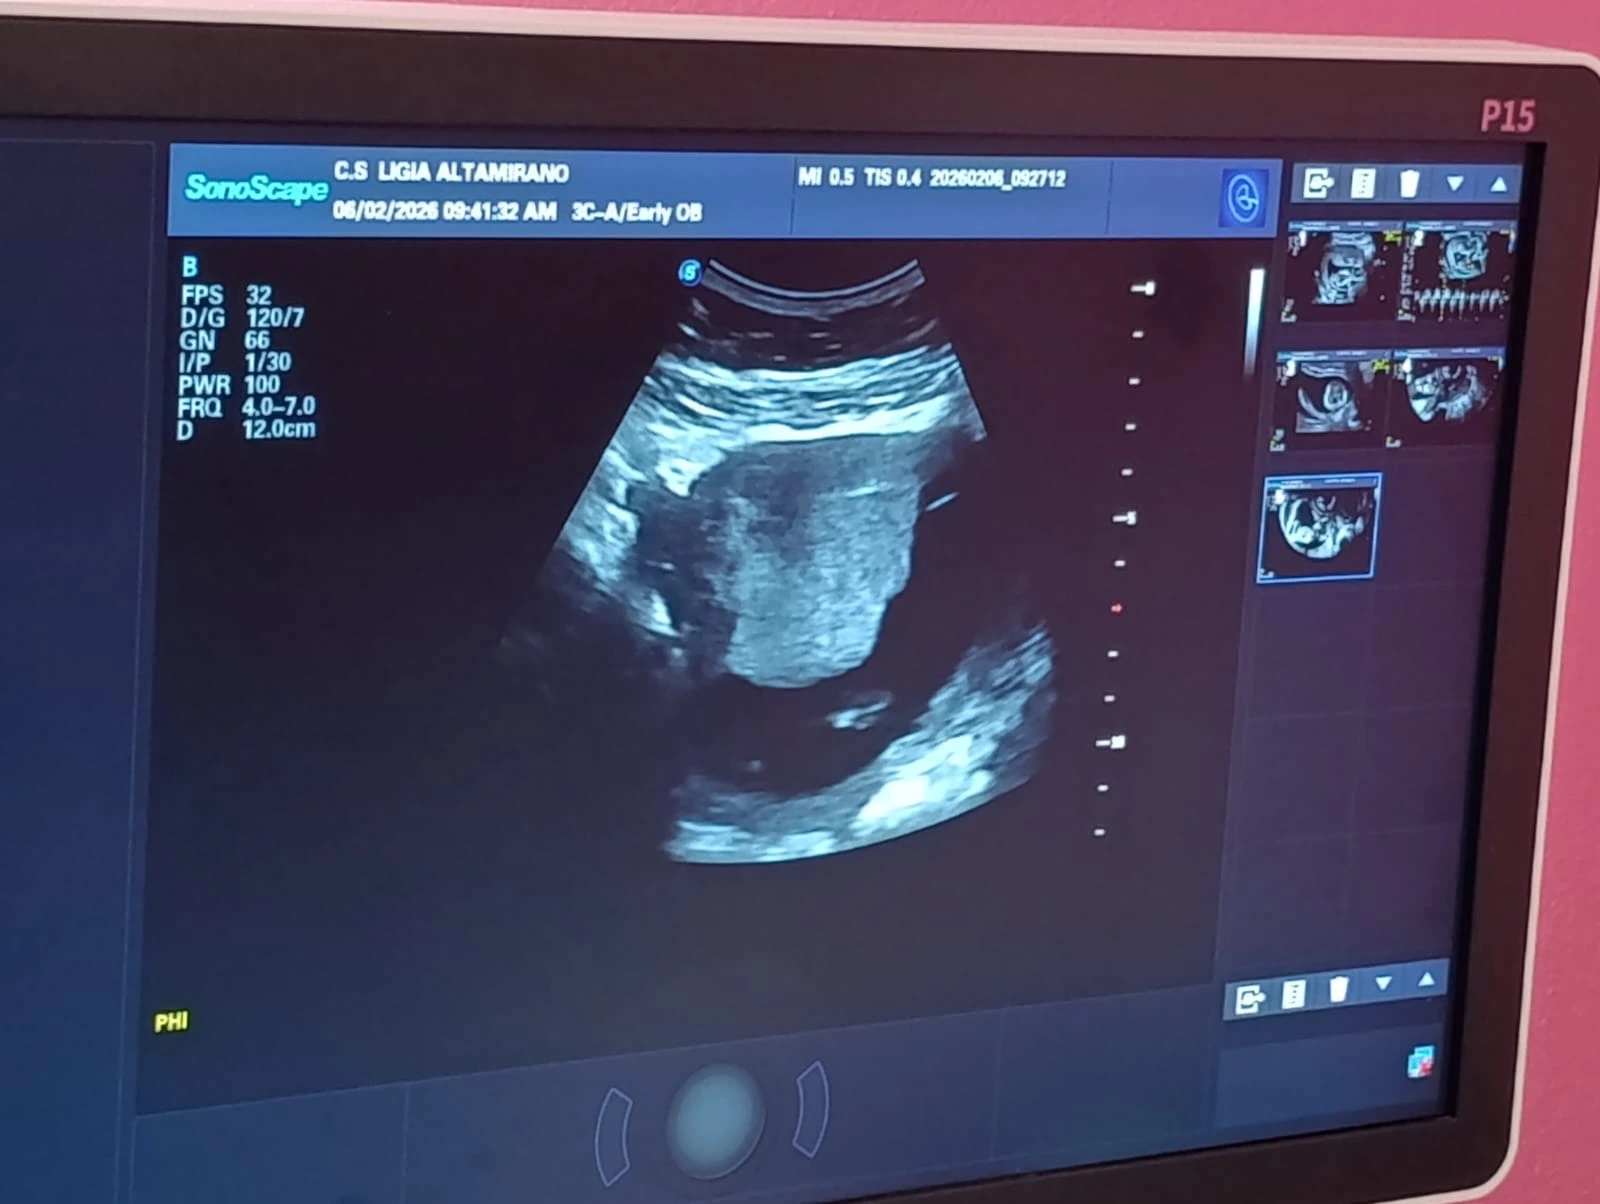

“Este estudio aplica la realización de un tamizaje del primer trimestre que consiste en la realización de ultrasonido obstétrico, en donde se valora la edad gestacional del bebé, y también se utiliza el tamizaje de arterias uterinas para valorar el riesgo a desarrollar preclampsia en la embarazada y, por último, lo que es la medición de la longitud cervical, que ayuda a valorar las pacientes que tienen un alto riesgo de desarrollar un parto pretérmino”, aseguró García.

En el Centro de Atención a la Mujer Doctora Ligia Altamirano, mujeres embarazadas del departamento de Managua recibieron atención médica integral en la feria de salud realizada con el fin de disminuir complicaciones tanto maternas como neonatales.

La doctora Judith García, ginecóloga y directora del Centro, indicó que todos los viernes atienden entre 100 y 150 embarazadas completamente gratis en este centro especial para la mujer.